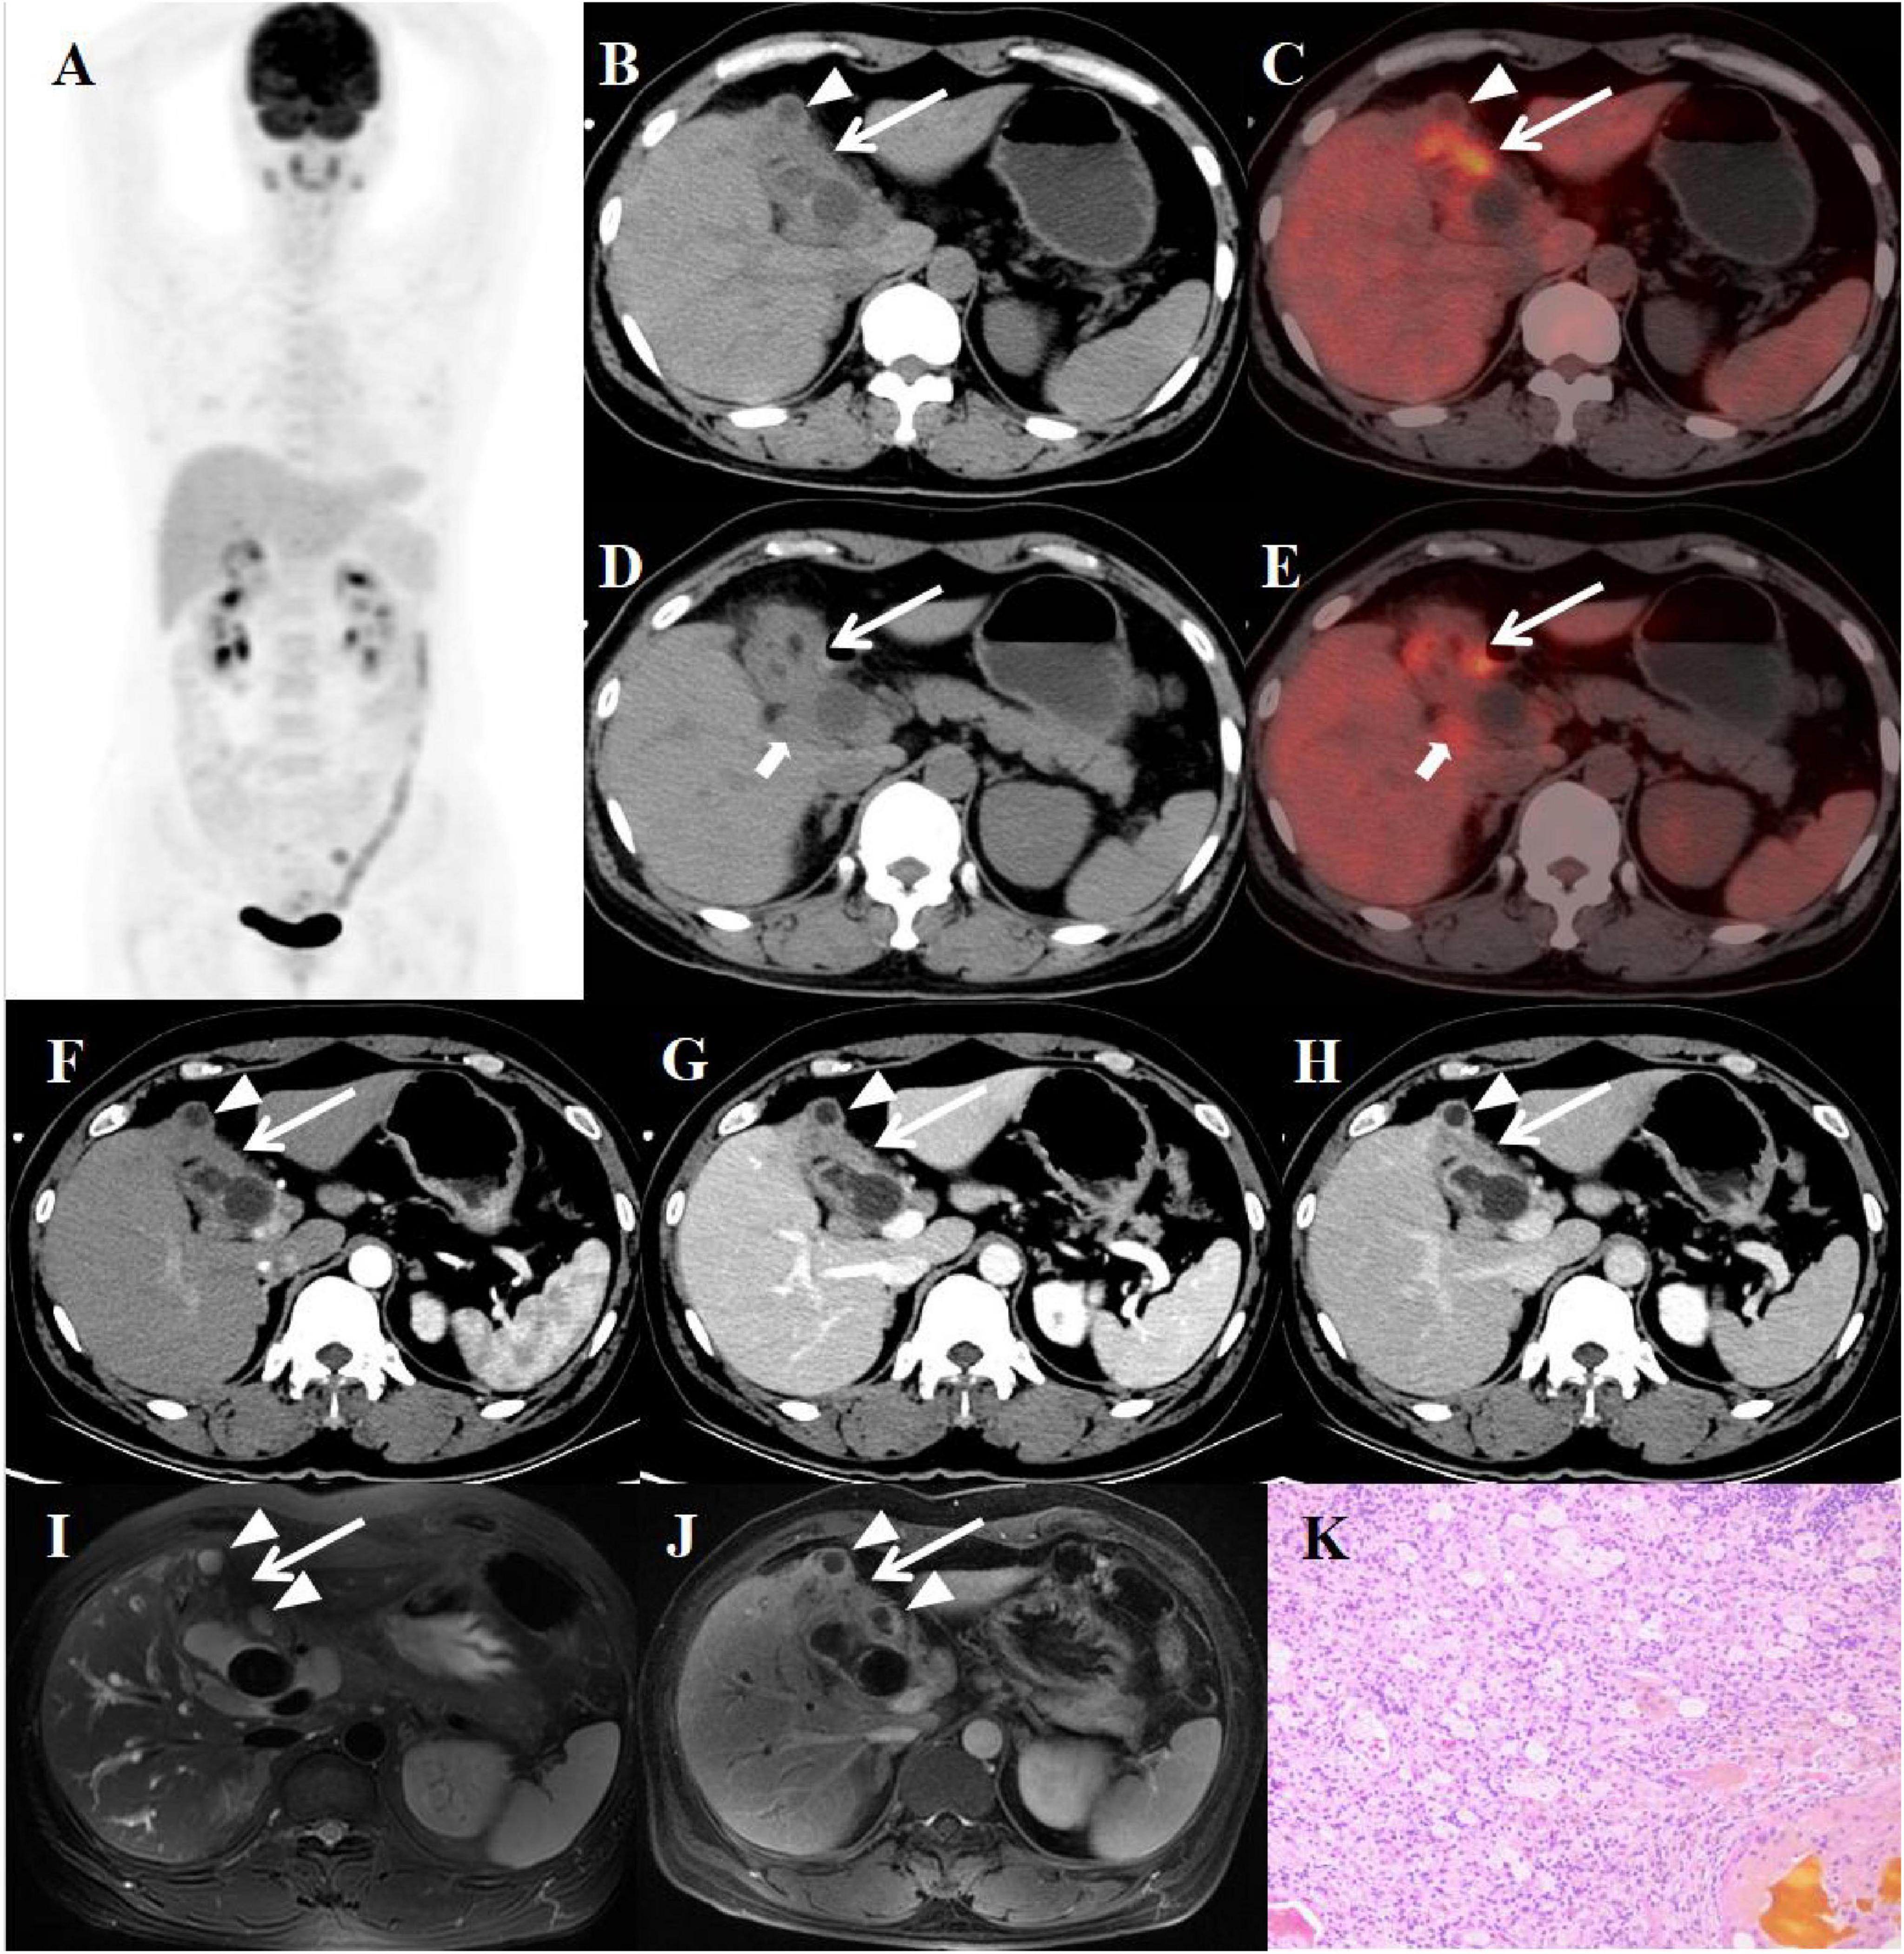

A 49-year-old female patient presented with abdominal pain, jaundice, and weight loss for 20 days before admission. An abdominal MRI scan performed at the local hospital disclosed an abnormal thickening of the gallbladder wall, accompanied by intramural nodules and the presence of enlarged pericholedochal lymph nodes. The boundary between the gallbladder and the liver was indistinct, with no evident signs of liver cirrhosis observed. Furthermore, the scan identified multiple stones within the gallbladder, a stone in the lower portion of the common bile duct, and compression of the upper part of the common bile duct, which led to the dilation of both intrahepatic and extrahepatic bile ducts above the obstruction. The multiphase contrast-enhanced scan images revealed that the thickened gallbladder wall shows mild enhancement during the arterial phase, with progressive enhancement observed in the venous and equilibrium phases. The intramural nodules displayed delayed rim enhancement. Despite undergoing treatments with anti-inflammatory and liver-protective agents at the local hospital, her symptoms showed no significant improvement. In response, a percutaneous transhepatic cholangiographic drainage (PTCD) was carried out. To further clarify the diagnosis and treatment plan, the patient was transferred to our hospital, where a comprehensive series of corresponding laboratory tests and imaging studies were conducted. The results of the inflammatory markers indicated that white blood cell count (WBC), neutrophile granulocyte, and C-reactive protein levels were all within normal limits, with procalcitonin was slightly elevated to 0.18 ng/ml. The levels of key tumor markers were as follows: Cancer Antigen 125 (CA-125) was elevated to 60.04 U/ml, while Cancer Antigen 19-9 (CA19-9) was significantly higher at 433.00 U/ml. Due to the patient’s recent PTCD procedure, the follow-up abdominal CT scan showed no evident obstruction or dilation of the bile ducts. The plain scan detected thickening of the gallbladder wall with low-density intramural nodules, surrounding enlarged lymph nodes, and stones in the gallbladder and the distal common bile duct. The enhancement pattern of the lesions on the contrast-enhanced scan was similar to that seen on the MRI. Subsequently, the patient underwent an PET/CT scan to evaluate the systemic condition. The axial CT and fused axial PET-CT images revealed asymmetric thickening of the gallbladder wall, accompanied by elevated fluorodeoxyglucose (FDG) uptake, with a maximum standardized uptake value (SUVmax) of 7.5. Enhanced FDG uptake was observed in several enlarged lymph nodes near the gallbladder fossa, reaching a SUVmax of 3.5. The intramural nodules showed no significant uptake of FDG (Figure 1). Given the imaging findings presented, a suspicion of GBC with hepatic invasion and lymph node metastasis was raised. After discussing the situation with his family, they agreed to proceed with a surgical procedure. The patient subsequently underwent a 5-hour-long procedure, comprising laparoscopic exploration, open partial hepatectomy (anatomical resection of segment IVB and V), choledochotomy, cholecystectomy, bilateral hepaticojejunostomy with Roux-en-Y anastomosis, and lymph node dissection. Considering the possibility of gallbladder cancer invading segment IV of the liver and the porta hepatis, and with no evidence of tumor metastasis in the other abdominal organs, an open abdominal surgical approach was undertaken for treatment. The intraoperative pathology evaluations uniformly pointed to chronic inflammation. Postoperative pathology confirmed the diagnosis of xanthogranulomatous cholecystitis, as well as reactive hyperplasia of regional lymph nodes.

Figure 1. Female, 49 years old. (A) (whole body MIP), (B–E) (Axial CT and fused axial PET-CT), (F–H) (axial, multiphasic contrast-enhanced CT), (I) (axial, MRI-T2WI), (J) (axial, enhanced-MRI-delayed phase), and (K) (H-E × 40). 18F-FDG PET/CT Imaging Findings: Thickening of the gallbladder wall with indistinct boundaries from the liver, accompanied by increased FDG uptake with a SUVmax of 7.5 (B–E, arrow). Additionally, several enlarged lymph nodes in the vicinity showed similar heightened FDG uptake, with an SUVmax of 3.5 (D, E, arrow ↑). The intramural nodules, however, did not display significant FDG uptake (B, C, arrow ▲). On multiphasic contrast-enhanced CT scans, there was progressive delayed enhancement of the gallbladder wall (F–H, arrow↑), along with marginal enhancement of the intramural nodules (arrow ↑). The CT values for the non-contrast scan phase, arterial phase, venous phase, and delayed phase were 40, 52, 75, and 89 HU, respectively. The abdominal MRI revealed irregular thickening of the gallbladder wall (I, arrow ↑) accompanied by gallstones. The intramural nodules appeared as hyper-intense on T2WI (arrow ▲). Contrast-enhanced imaging demonstrated delayed enhancement of the gallbladder wall (J, arrow ↑), with rim-enhancement of the intramural nodules (arrow ▲). Histopathological analysis confirmed XGC, showing foamy histiocytes intermingled with scattered lymphocytes, encircled by phagocytosed bile, in the absence of malignant cells (K).